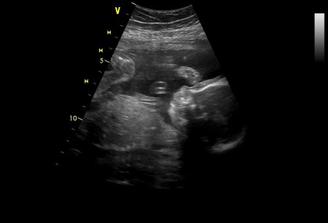

°°°°28.2.2009 00:10hod som bola hospitalizovaná s velkými bolesťami v bříšku,krvácením kvuli hematomu ☹ poriadne nás to vystrašilo,takže už zostávam doma a žiadna námaha ani stres nehrozia...už sme tu týždeň,tak snáď nás zajtra 6.3.pustia domkov a bude to v poriadku.Jediné,čo ma potešili bolo,že som videla prcka-no a je to teda divoch 🙂

°°°°6.3.tak nás pustili domkov na priepustku,musíme sa ukázať 13.3.na kontrolu,sice nám zistili kvasinky,ale dali nám vagin.lieky na týždeň,tak verím,že piatok 13teho bude šťastný 🙂,inak na kontrolnom uzv sme videli,že hematom je už polovičný,čo je úžasné,pani doktorka mi prcka zase zmerala a ukázala orgány,keď sa dostala ku stehennej kosti a močovému mechúru,tak sme zistili,že máme nestydu 🙂,pani dr.sa smiala,že už chápe,prečo tak rozťahuje nožičky,ukazuje nám totiž hrdo,na čo je pyšný 🙂 °°°°budeme mať CHLAPČEKA 🙂°°°°